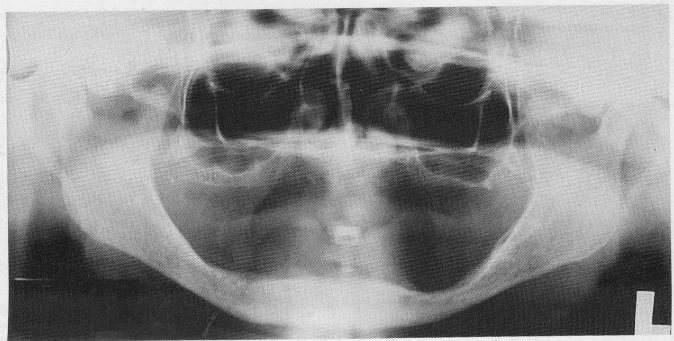

Why do we still take radiographs on edentulous clients?

1. To detect any root tips, impacted teeth, cysts, tumours

2. to identify objects, embedded in alveolar bone

3. to establish position of normal anatomic landmarks

4. to observe quantity and quality of existing bone